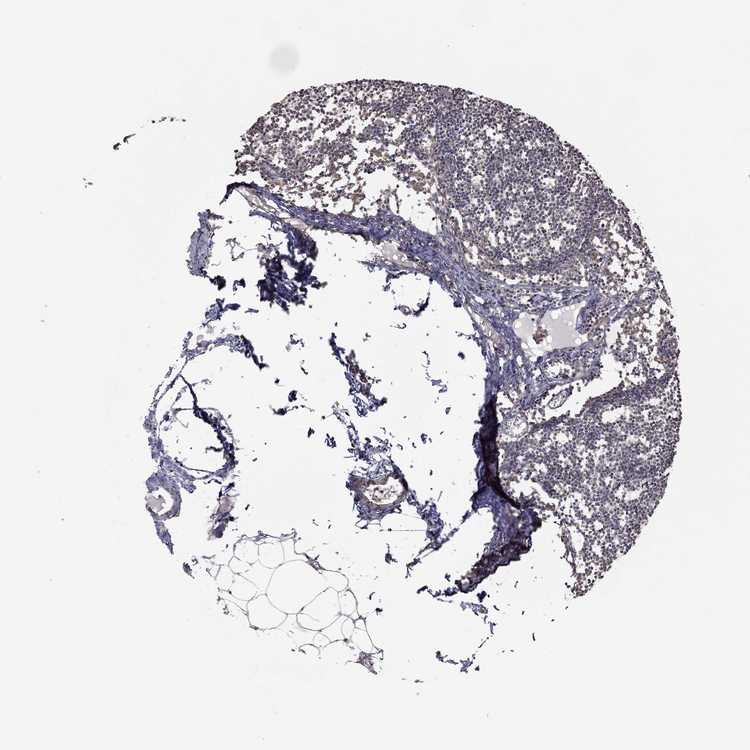

TISSUE PRIMARY DATA LYMPH NODE Show tissue menu

LYMPH NODE - Antibody stainingi

Antibody staining in the annotated cell types in the current human tissue is reported as not detected, low, medium, or high, based on conventional immunohistochemistry profiling in selected tissues. This score is based on the combination of the staining intensity and fraction of stained cells.

Each image is clickable and will lead to virtual microscopy that enables deeper exploration of all samples and also displays staining intensity scores, fraction scores and subcellular localization as well as patient and tissue information for each sample.

Antibody HPA071317

Germinal center cells Not detected

Non-germinal center cells Not detected